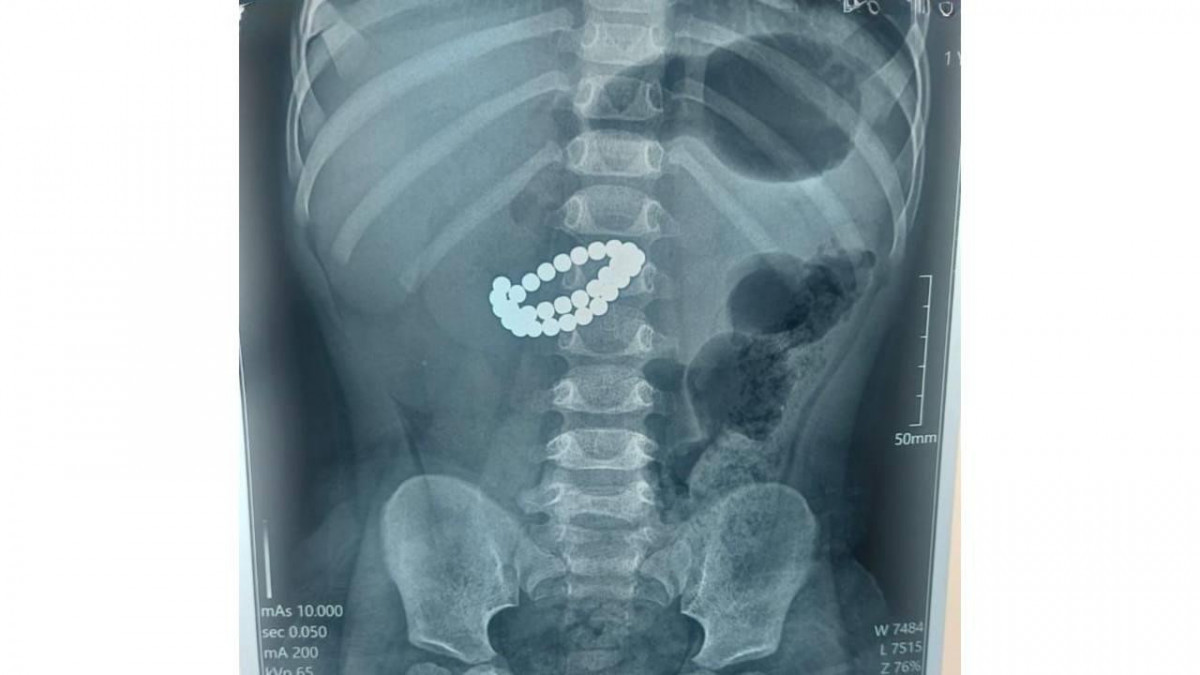

Фото: Алматы қ. Денсаулық сақтау басқармасы

Қоғамдық денсаулық сақтау басқармасының өкілдерінің хабарлауынша, Алматының Балаларға шұғыл медициналық көмек көрсету орталығында 31 магнит жұтып қойған сәбиге шұғыл ота жасалды.

Қабылдау бөліміне 1 жас 9 айлық бала өте ауыр жағдайда жеткізілген. Тексеру нәтижесінде дәрігерлер "ішектегі бөгде заттар – 31 магнит, жіңішке ішектің көп жерден тесілуі, перитонит" диагнозын қойды.

Баланың өмірін сақтап қалудың жалғыз жолы – шұғыл хирургиялық ота жасау еді. Дәрігерлер ортаңғы лапаротомия жасап, құрсақ қуысы ағзаларына толық тексеру жүргізді. Ота барысында магниттер ішектен алынып, жіңішке ішектегі көптеген тесік тігілді, құрсақ қуысы тазартылып, дренаж орнатылды. Сонымен қатар ішекке трансаналдық интубация жасалды, - делінген хабарламада.